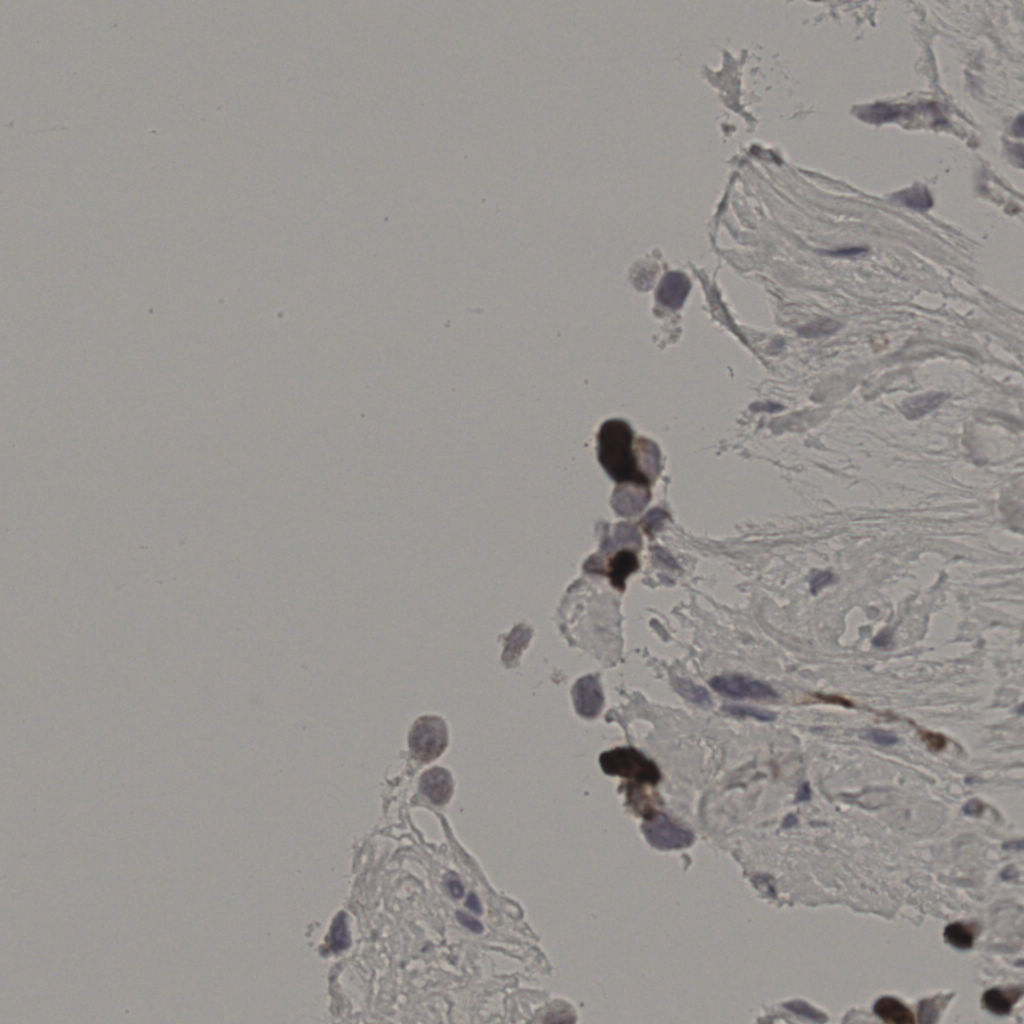

缩略图

标记后

标记前